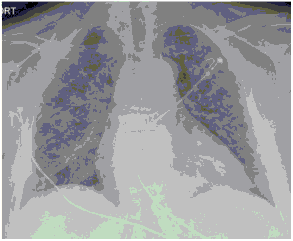

Методы лучевой диагностики применяют для выявления COVID-19 пневмоний, их осложнений, дифференциальной диагностики с другими заболеваниями легких, а также для определения степени выраженности и динамики изменений, оценки эффективности проводимой терапии.

К методам лучевой диагностики патологии ОГК пациентов с предполагаемой/установленной COVID-19 пневмонией относят:

- Обзорную рентгенографию легких (РГ),

- Компьютерную томографию легких (КТ),

- Ультразвуковое исследование легких и плевральных полостей (УЗИ).

Стандартная РГ имеет низкую чувствительность в выявлении начальных изменений в первые дни заболевания и не может применяться для ранней диагностики. Информативность РГ повышается с увеличением длительности течения пневмонии. Рентгенография с использованием передвижных (палатных) аппаратов является основным методом лучевой диагностики патологии ОГК в ОРИТ. Применение передвижного (палатного) аппарата оправдано и для проведения обычных РГ исследований в рентгеновском кабинете. В стационарных условиях относительным преимуществом РГ в сравнении с КТ являются большая пропускная способность. Метод позволяет уверенно выявлять тяжелые формы пневмоний и отек легких различной природы, которые требуют госпитализации, в том числе направления в ОРИТ.

КТ имеет высокую чувствительность в выявлении изменений в легких, характерных для COVID-19. Применение КТ целесообразно для первичной оценки состояния ОГК у пациентов с тяжелыми прогрессирующими формами заболевания, а также для дифференциальной диагностики выявленных изменений и оценки динамики процесса. КТ позволяет выявить характерные изменения в легких у пациентов с COVID-19 еще до появления положительных лабораторных тестов на инфекцию с помощью МАНК. В то же время, КТ выявляет изменения легких у значительного числа пациентов с бессимптомной и легкой формами заболевания, которым не требуется госпитализация. Результаты КТ в этих случаях не влияют на тактику лечения и прогноз заболевания при наличии лабораторного подтверждения COVID-19. Поэтому массовое применение КТ для скрининга асимптомных и легких форм болезни не рекомендуется. При первичном обращении пациента с подозрением на COVID-19 рекомендуется назначать КТ только при наличии клинических и инструментальных признаков дыхательной недостаточности (SpO2 < 95%, ЧДД > 22).